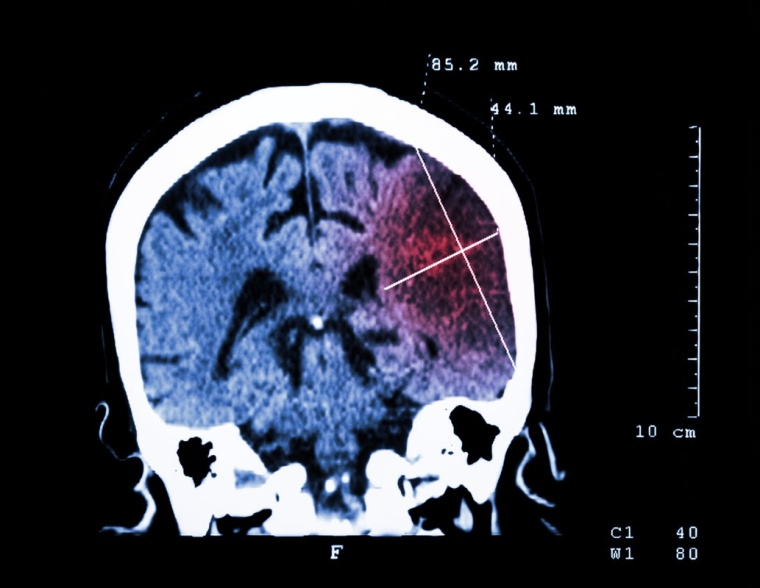

Delir bei Schlaganfallpatienten

Verwirrtheit, Wahrnehmungsstörungen, Unruhe – dies sind typische Symptome, die ein Delir ausmachen können. In der Frühphase nach einem Schlaganfall kommt es bei 15 bis 25 % aller Patienten zu diesem Zustand.